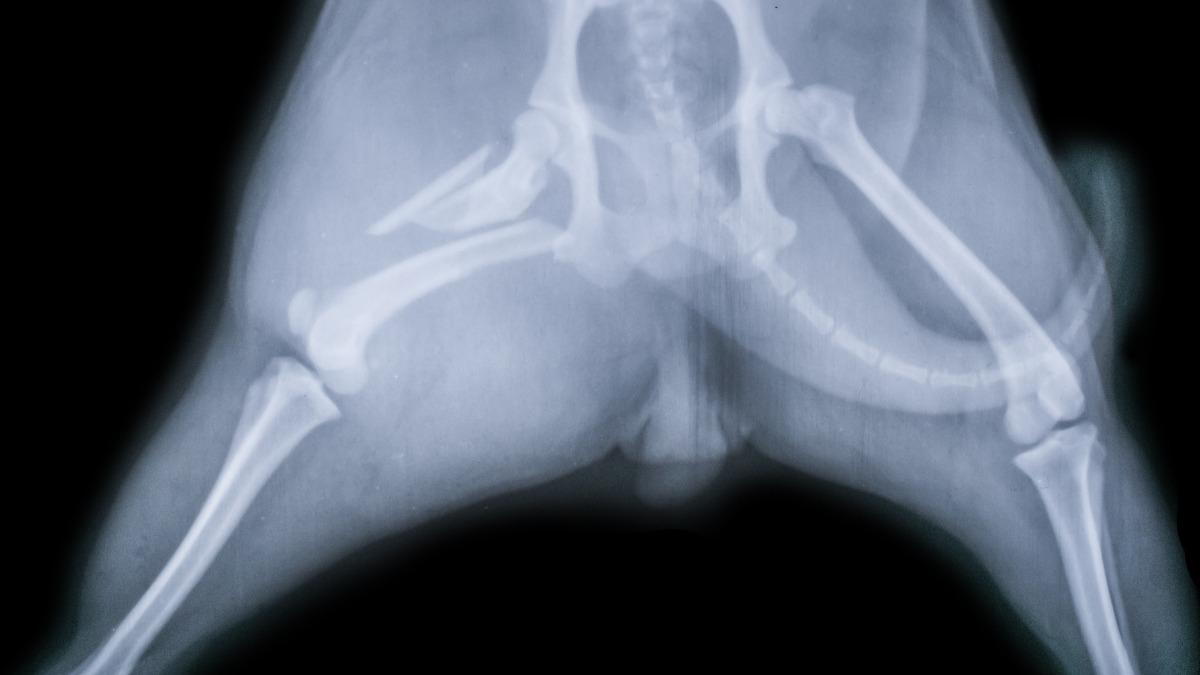

When your pet experiences an injury, x-rays provide a clear view of the affected area, enabling precise diagnosis. Whether it’s a suspected fracture, a swallowed foreign object, or a suspected internal injury, x-rays guide our veterinarian in choosing the best treatment path. This accuracy helps reduce recovery time and minimizes the risk of complications.

One of the primary benefits of regular pet x-rays is the early detection of hidden health issues. Conditions such as bone fractures, arthritis, tumors, or dental problems can develop without obvious signs. By taking x-rays during routine visits, our veterinarian can identify these concerns before they worsen, allowing for timely intervention and better outcomes for your pet.

Pets with chronic health problems like heart disease or joint disorders benefit significantly from regular x-rays. These images help track disease progression and assess how well treatments are working. At Oaks North Animal Hospital, we use pet x-rays to adjust care plans as needed, ensuring your pet remains comfortable and receives the most effective therapies.